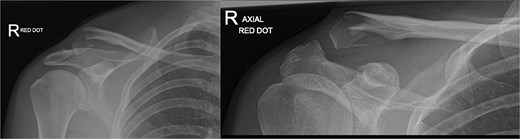

A 30-year-old male presented with an unstable lateral clavicle fracture and skin tenting after a rugby injury. Imaging revealed a Neer type IV equivalent fracture (Fig. 3). He underwent open reduction and internal fixation with coracoid exposure and TightRope placement, reinforced with fiber-wire. Postoperative recovery included sling immobilization followed by pendular exercises. Despite delayed radiological union, he achieved full range of motion and strength by three months, with only mild, asymptomatic clavicular prominence. He returned to physically demanding work without restrictions, and final imaging confirmed union (Fig. 4A–C).

(A–C) Radiographs showing complete healing of the second case and union at 3, 6, and 12 months post-operatively.